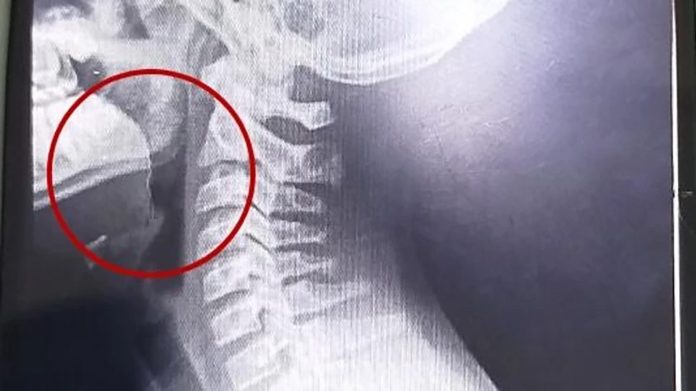

El hospital Materno Infantil de Mar del Plata halló mediante estudios por imágenes un alambre fino incrustado en la garganta del paciente (0223)

A continuación, se desarrollaron distintos estudios para descartar la presencia de infecciones o bacterias, cuyos resultados resultaron negativos. La clave para entender el cuadro apareció tras la realización de estudios por imágenes: las placas evidenciaron la presencia de un objeto extraño alojado en la vía aérea superior.

El parte médico consignó que el paciente ingresó “clínica y hemodinámicamente estable, afebril, vigil, reactivo, normohidratado y normoperfundido”, según el medio local. Luego de una interconsulta con el servicio de otorrinolaringología, se resolvió su ingreso urgente a quirófano. Allí, el equipo médico halló un alambre fino incrustado en la garganta del adolescente, situación que no había sido advertida previamente.